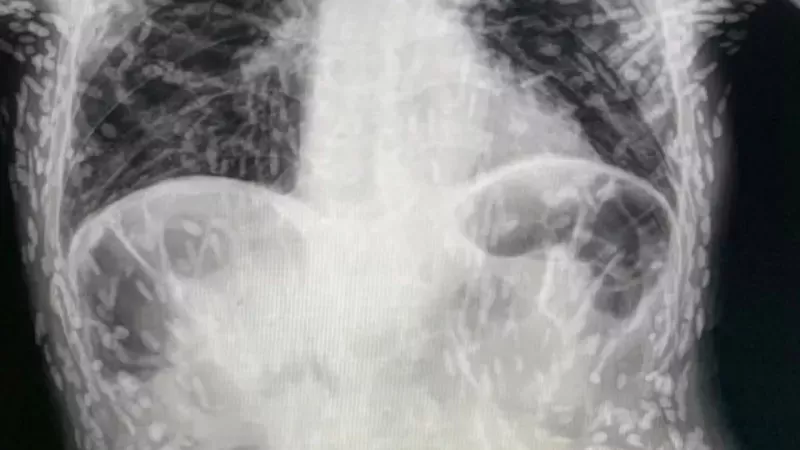

Brezilya'da yaşanan korkunç bir olay, yiyeceklerin iyice yıkanmasının ne kadar önemli olduğunu bir kez daha gözler önüne serdi. Şiddetli öksürük şikâyetiyle hastaneye başvuran bir kişinin midesinde onlarca tenya larvası olduğu tespit edildi. Bu durum, domuz tenyası larva kistlerinin beyin ve göz dokusuna ulaşması sonucunda yaşanan ölümcül enfeksiyonlara dikkat çekiyor. Bu nedenle uzmanlar, yiyeceklerin özellikle de et ürünlerinin iyice yıkanması gerektiğini belirtiyorlar. Sağlıklı bir yaşam için hijyen kurallarına uygun davranmak büyük önem taşıyor.

Brezilya'da yaşanan ölümcül tenya vakası, yiyeceklerin iyice yıkanması gerektiğini hatırlattı. Tenya larvaları, girdikleri dokularda kist oluşumuna neden olur ve ölümcül sonuçlara yol açabilirler. Dünya Sağlık Örgütü, epilepsi vakalarının yüzde 70'inin domuz tenyası larvalarından kaynaklandığını tahmin ediyor. Bu nedenle, tüm dünyada insanların tenyalara karşı yeterli bilgiye sahip olmaları gerekiyor.

Domuz tenyası, bağırsaklarda yaşar ve dışkı yoluyla yayılır. Eğer yiyecekler yeterince yıkanmazsa veya doğru şekilde pişirilmezse, tenya larvaları insana bulaşabilir. Bu larvalar, kas veya beyin gibi dokulara yerleşerek kist oluşumuna neden olurlar. Kistlerin büyümesi, ciddi sağlık sorunlarına yol açabilir ve hatta ölüme neden olabilir.